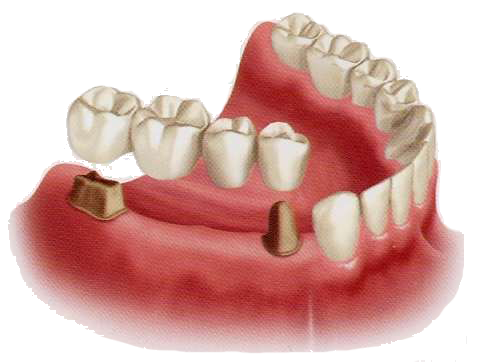

传统的镶牙技术包括两大类:做活动假牙或固定假牙。活动假牙也叫活动义齿、可摘义齿,用挂钩固定在缺失牙旁边的余留牙齿上。固定假牙也叫固定义齿,一般是做烤瓷牙。

(二)传统修复 Vs 种植修复

传统修复 | 种植修复 | |

固定修复 | 活动修复 | |

1·对口内相关健康邻牙牙体磨除量大,损伤不可逆;

| 1·体积大,有异物感,舒适感差; 2·仅能恢复天然牙30%左右的咀嚼功能; 3·使用寿命短,一般为5年左右就要更换; 4·持续佩戴会造成牙槽骨的进一步吸收。 | 优点: 1·能够最大限度地恢复患者的口腔功能; 4·舒适感好,没有没有味觉迟钝与不适感; 5·能保存牙槽骨,防止萎缩; 6·寿命长; 7·操作简单,创伤小,采用局麻,几乎无痛苦;